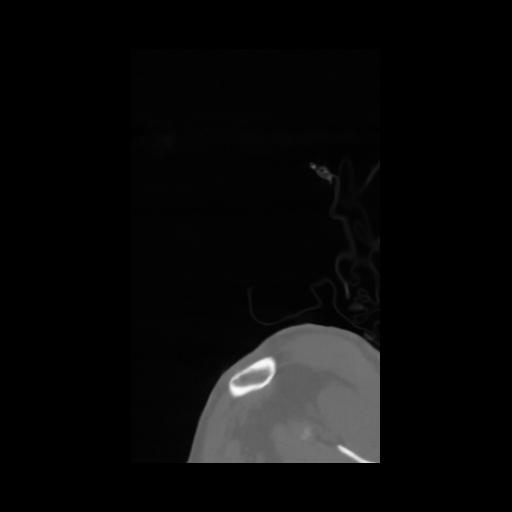

14 P.BLANDAS,,Sagittal,2.000,P.BLANDAS,Sagittal,